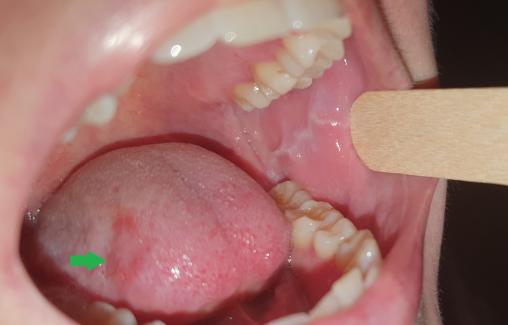

Lydie, 24 ans, consulte pour des stries de couleur blanche apparues depuis quelques jours au niveau de la face interne des deux joues (figure). Elle est inquiète car ces lésions ressemblent à celles de son père, traité pour un cancer de la langue. Elle explique se brosser les dents 4 ou 5 fois par jour en traumatisant parfois la muqueuse buccale et la langue (figure, flèche verte), anxieuse depuis le diagnostic posé chez son père.

Cliniquement, une ligne blanche horizontale surélevée est observée ; elle est parfois saillante du fait de l’épaississement de la couche cornée. Elle se situe classiquement sur la partie moyenne de la muqueuse jugale au niveau de la ligne d’occlusion dentaire ; l’atteinte est, dans la plupart des cas, bilatérale. Une extension est parfois possible vers la commissure des lèvres sur la partie antérieure, et jusqu’au niveau des dernières molaires sur la partie postérieure. Une forme similaire de ligne blanche peut être observée sur les bords latéraux de la langue.